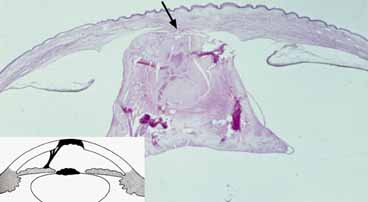

POSTERIOR CORNEAL DEFECT (STUMPED)

A central or paracentral corneal opacity is the clinical hallmark for the group of congenital abnormalities known as posterior corneal defects. Common histopathological findings include focal attenuation or complete absence of the endothelium and Descemet's membrane behind the overlying opacity. These disorders are part of a group of anomalies referred to as anterior segment mesenchymal dysgenesis or the anterior chamber cleavage syndrome.107,108 Embryologically, these conditions are likely the result of abnormal neural crest cell development.21 A descriptive anatomic stepladder classification scheme (Fig. 15) was developed to help categorize these conditions from simple to more complex forms.108 This classification scheme allows clinicians and pathologists to describe the anatomic findings without the use of eponyms and Latin phrases.

CORNEAL STAPHYLOMA

Corneal staphyloma is a severe form of posterior corneal defect in which the cornea becomes anteriorly ectatic and protrudes forward through the palpebral fissure (Fig. 23).134 Either the malformation itself or the associated elevated intraocular pressure causes the anterior displacement of the cornea. This condition is usually unilateral. The thin, scarred, vascularized cornea has a blue color because of the underlying uveal tissue and may become keratinized secondary to exposure. In rare instances, the cornea develops a hypertrophic keloid scar.135

Fig. 23 Corneal staphyloma. A. Enucleated globe demonstrates marked ectasia of entire cornea. Cornea protruded between the eyelids at time of birth. B. Histopathology shows focal thinning of the cornea and vascularization with adherent shrunken lens. Clilary processes adhere to posterior lens. Atrophic iris (arrows) lines cornea and lens stalk (Hematoxylin-eosin, ×4). (Waring GO, Rodrigues MM, Laibson PR: Anterior chamber cleavage syndrome. Surv Ophthalmol 20:3–27, 1975)

Histopathologically, the epithelium shows central keratinization.136 There are also fragmented breaks in an attenuated Bowman's membrane. The corneal stroma is thin, disorganized, and vascularized. The endothelium and Descemet's membrane are absent and the posterior cornea is lined by atrophic iris tissue (Fig. 23B).136